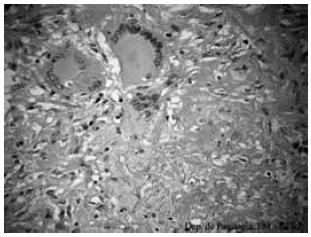

Considere a imagem de uma célula:

Essa célula é conhecida como célula